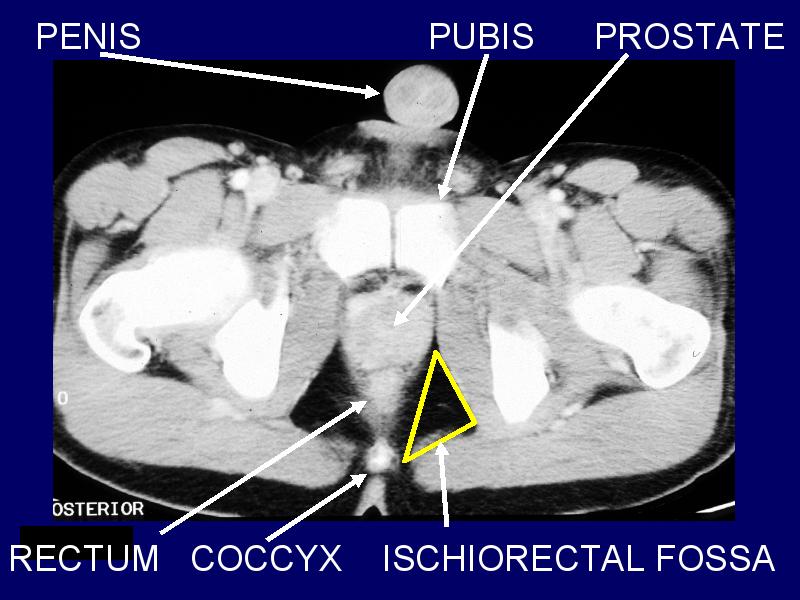

MS 204 MALE PELVIS 2